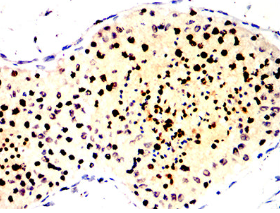

RBMXL3 Mouse Monoclonal antibody[1B6F4]

RBMXL3 (RBMX Like 3) is a Protein Coding gene. Diseases associated with RBMXL3 include Cardiomyopathy, Familial Restrictive, 3. Among its related pathways are mRNA Splicing - Major Pathway. Gene Ontology (GO) annotations related to this gene include nucleic acid binding and nucleotide binding. An important paralog of this gene is RBMXL2.

Immunogen:    Purified recombinant fragment of human RBMXL3(AA: 862-1067) expressed in E. Coli.

IHC    1/200 - 1/1000